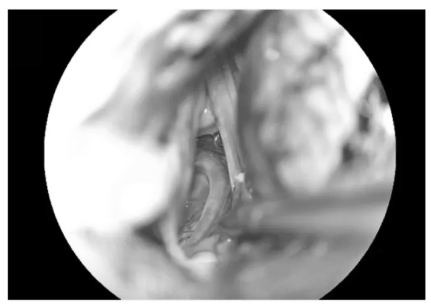

▼充分游離后組顱神經(jīng)與絨球

充分游離后組顱神經(jīng)與絨球

▼逐步暴露椎動(dòng)脈、PICA及延髓側(cè)方

逐步暴露椎動(dòng)脈、PICA及延髓側(cè)方

▼分離延髓表面血管

分離延髓表面血管

▼從后組顱神經(jīng)與PICA之間進(jìn)入延髓側(cè)方

從后組顱神經(jīng)與PICA之間進(jìn)入延髓側(cè)方

▼可見(jiàn)黃染的含鐵血黃素沉積帶

可見(jiàn)黃染的含鐵血黃素沉積帶

▼可見(jiàn)粗大的引流靜脈,予以保護(hù)

可見(jiàn)粗大的引流靜脈,予以保護(hù)

▼沿周邊黃染的含鐵血黃素沉積帶分離腫瘤

沿周邊黃染的含鐵血黃素沉積帶分離腫瘤

▼腫瘤標(biāo)本完整取出

腫瘤標(biāo)本完整取出

▼瘤腔止血

瘤腔止血

▼袖珍的延髓表面造痿口

袖珍的延髓表面造痿口

▼水密縫合硬腦膜

水密縫合硬腦膜